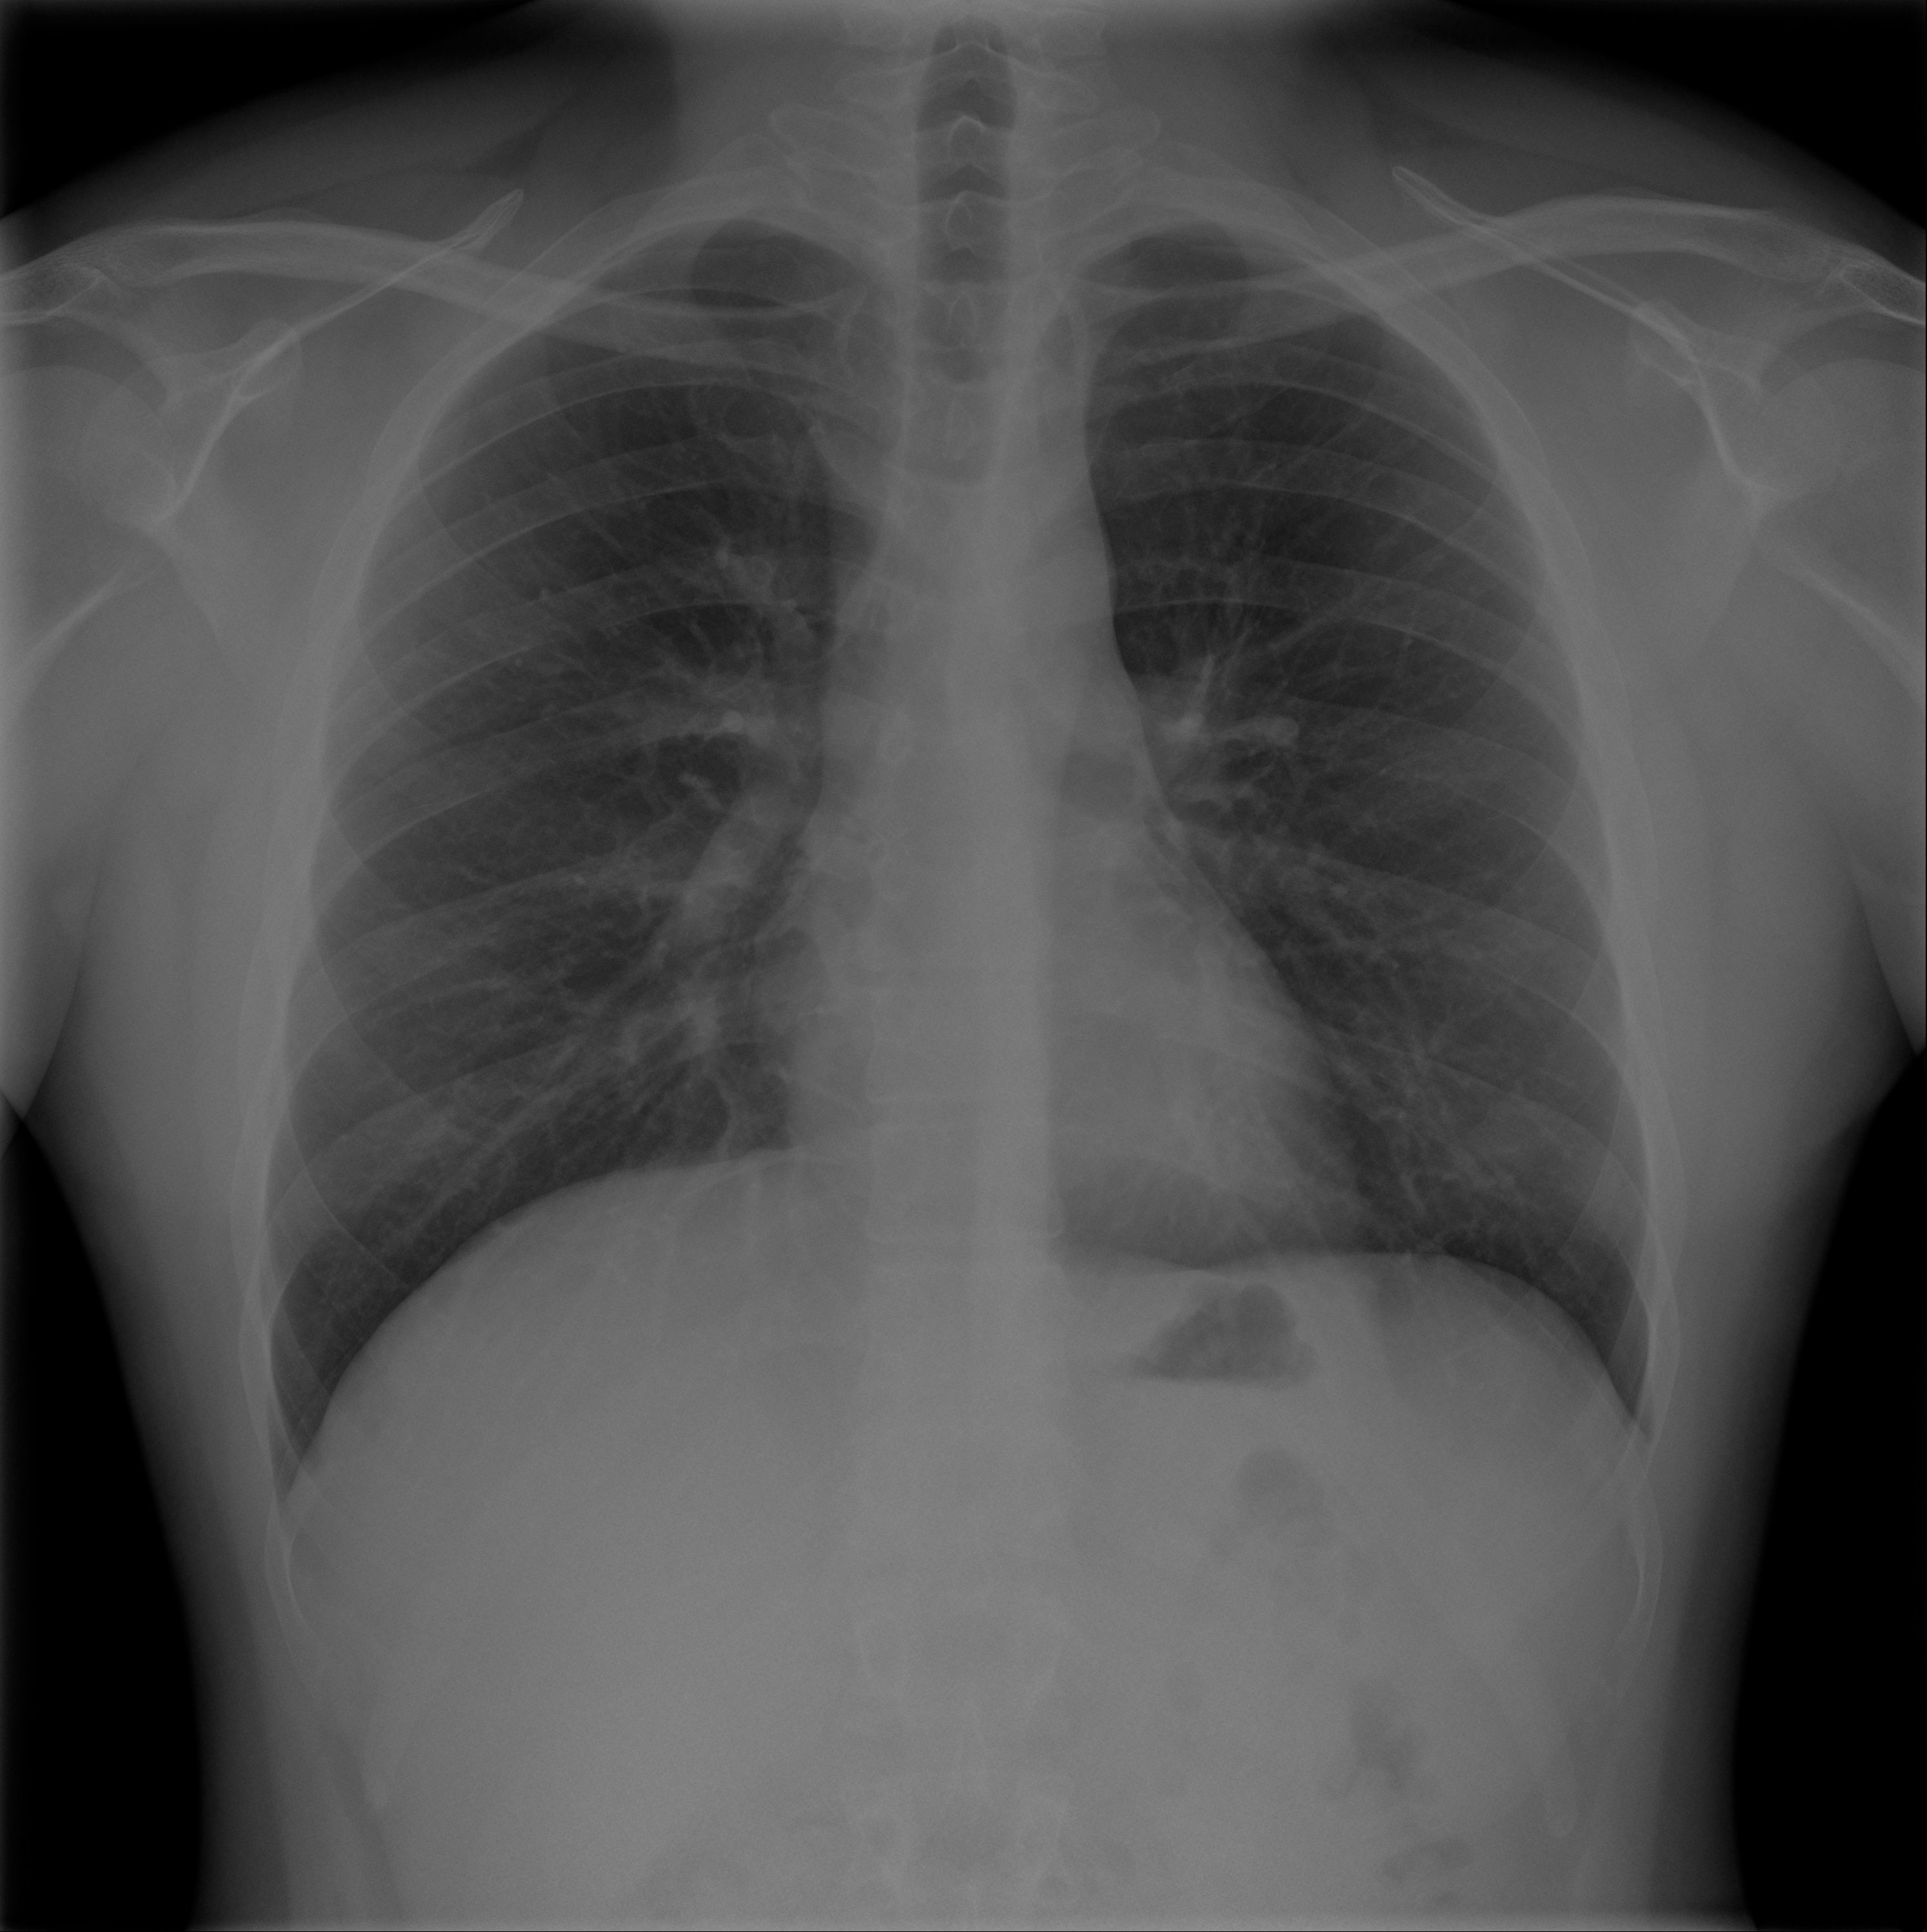

Un nuevo avance científico pondrá patas arribas las radiografías de tórax. Un equipo de investigación de la Universitat Jaume I de Castelló y la Fundación para el Fomento de la Investigación Sanitaria y Biomédica de la Comunitat Valenciana (Fisabio), con la colaboración del Servicio de Radiodiagnóstico del Hospital General Universitario de Castellón (HGUCS), ha desarrollado una herramienta para la detección automática de patologías en radiografías de tórax basada en la experiencia y los conocimientos del personal de radiología que se validan a partir del análisis automático de informes médicos.

El nuevo sistema inteligente de apoyo al radiodiagnóstico, basado en técnicas de computación de inteligencia artificial (IA) y en el tratamiento de grandes volúmenes de datos (big data), tiene por objetivo identificar la patología urgente en radiografías de tórax en adultos y así priorizar la realización del informe por el especialista en radiología, lo que permitiría implantar un sistema de triaje radiológico. Con ello se espera conseguir una gestión más ágil de los casos urgentes procedentes del Servicio de Urgencias del HGUCS.

El software consta de un módulo para la detección de patologías en radiografías de tórax, que podrá extenderse en un futuro con otros módulos para la identificación de patologías en otro tipo de imágenes médicas. Para ello, el sistema recibe imágenes anónimas de los centros médicos y responde con una predicción de las patologías halladas. La colaboración del personal de radiología en el desarrollo ha permitido utilizar sus conocimientos y su experiencia para reforzar el aprendizaje de los algoritmos de inteligencia artificial utilizados.